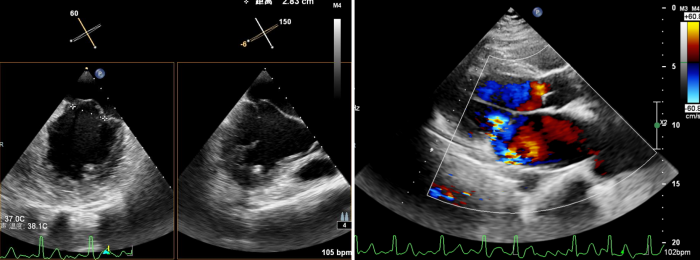

术前,超声科聂红军教授运用全数字化高端心脏彩色多普勒诊断仪,为患者进行食道三维超声综合评估,确定了二尖瓣返流量及返流分区。同时,在手术中实时监测二尖瓣瓣叶返流区与钳夹器的位置是否吻合,术后还可即刻探查二尖瓣返流量减少情况,如果把手术比作开车,那超声科就是手术的导航系统。

术中,蒋路平主任团队在经食道超声引导下通过股静脉穿刺房间隔将二尖瓣钳夹系统送入患者左心房到达二尖瓣口,然后医生全程在经食道超声引导下通过评估二尖瓣返流位置以及返流程度等精准夹合二尖瓣叶,整个过程都是在心脏不停跳的情况下完成。

术前心脏彩超所示:二尖瓣返流